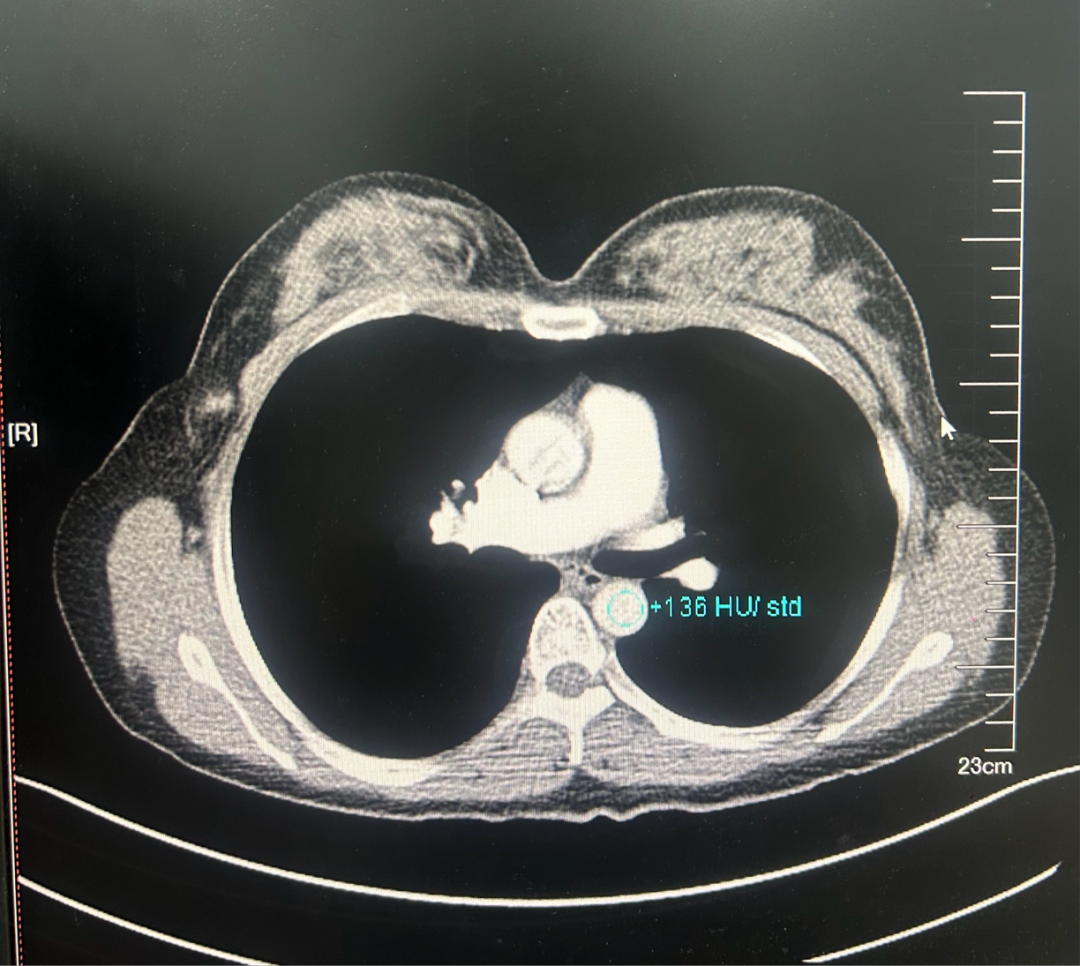

·乳腺彩超

2023-06-26彩色多普勒超声宽景成像+术前体表定位:

1、左乳4点钟方向实性肿块(乳腺Ca可能,BI-RADS 4C类),已体表定位,此次定位仅供手术医生参考。

2、双乳乳腺增生症。

3、双侧腋窝探及多个淋巴结。

图1.2023年6月24日乳腺彩超